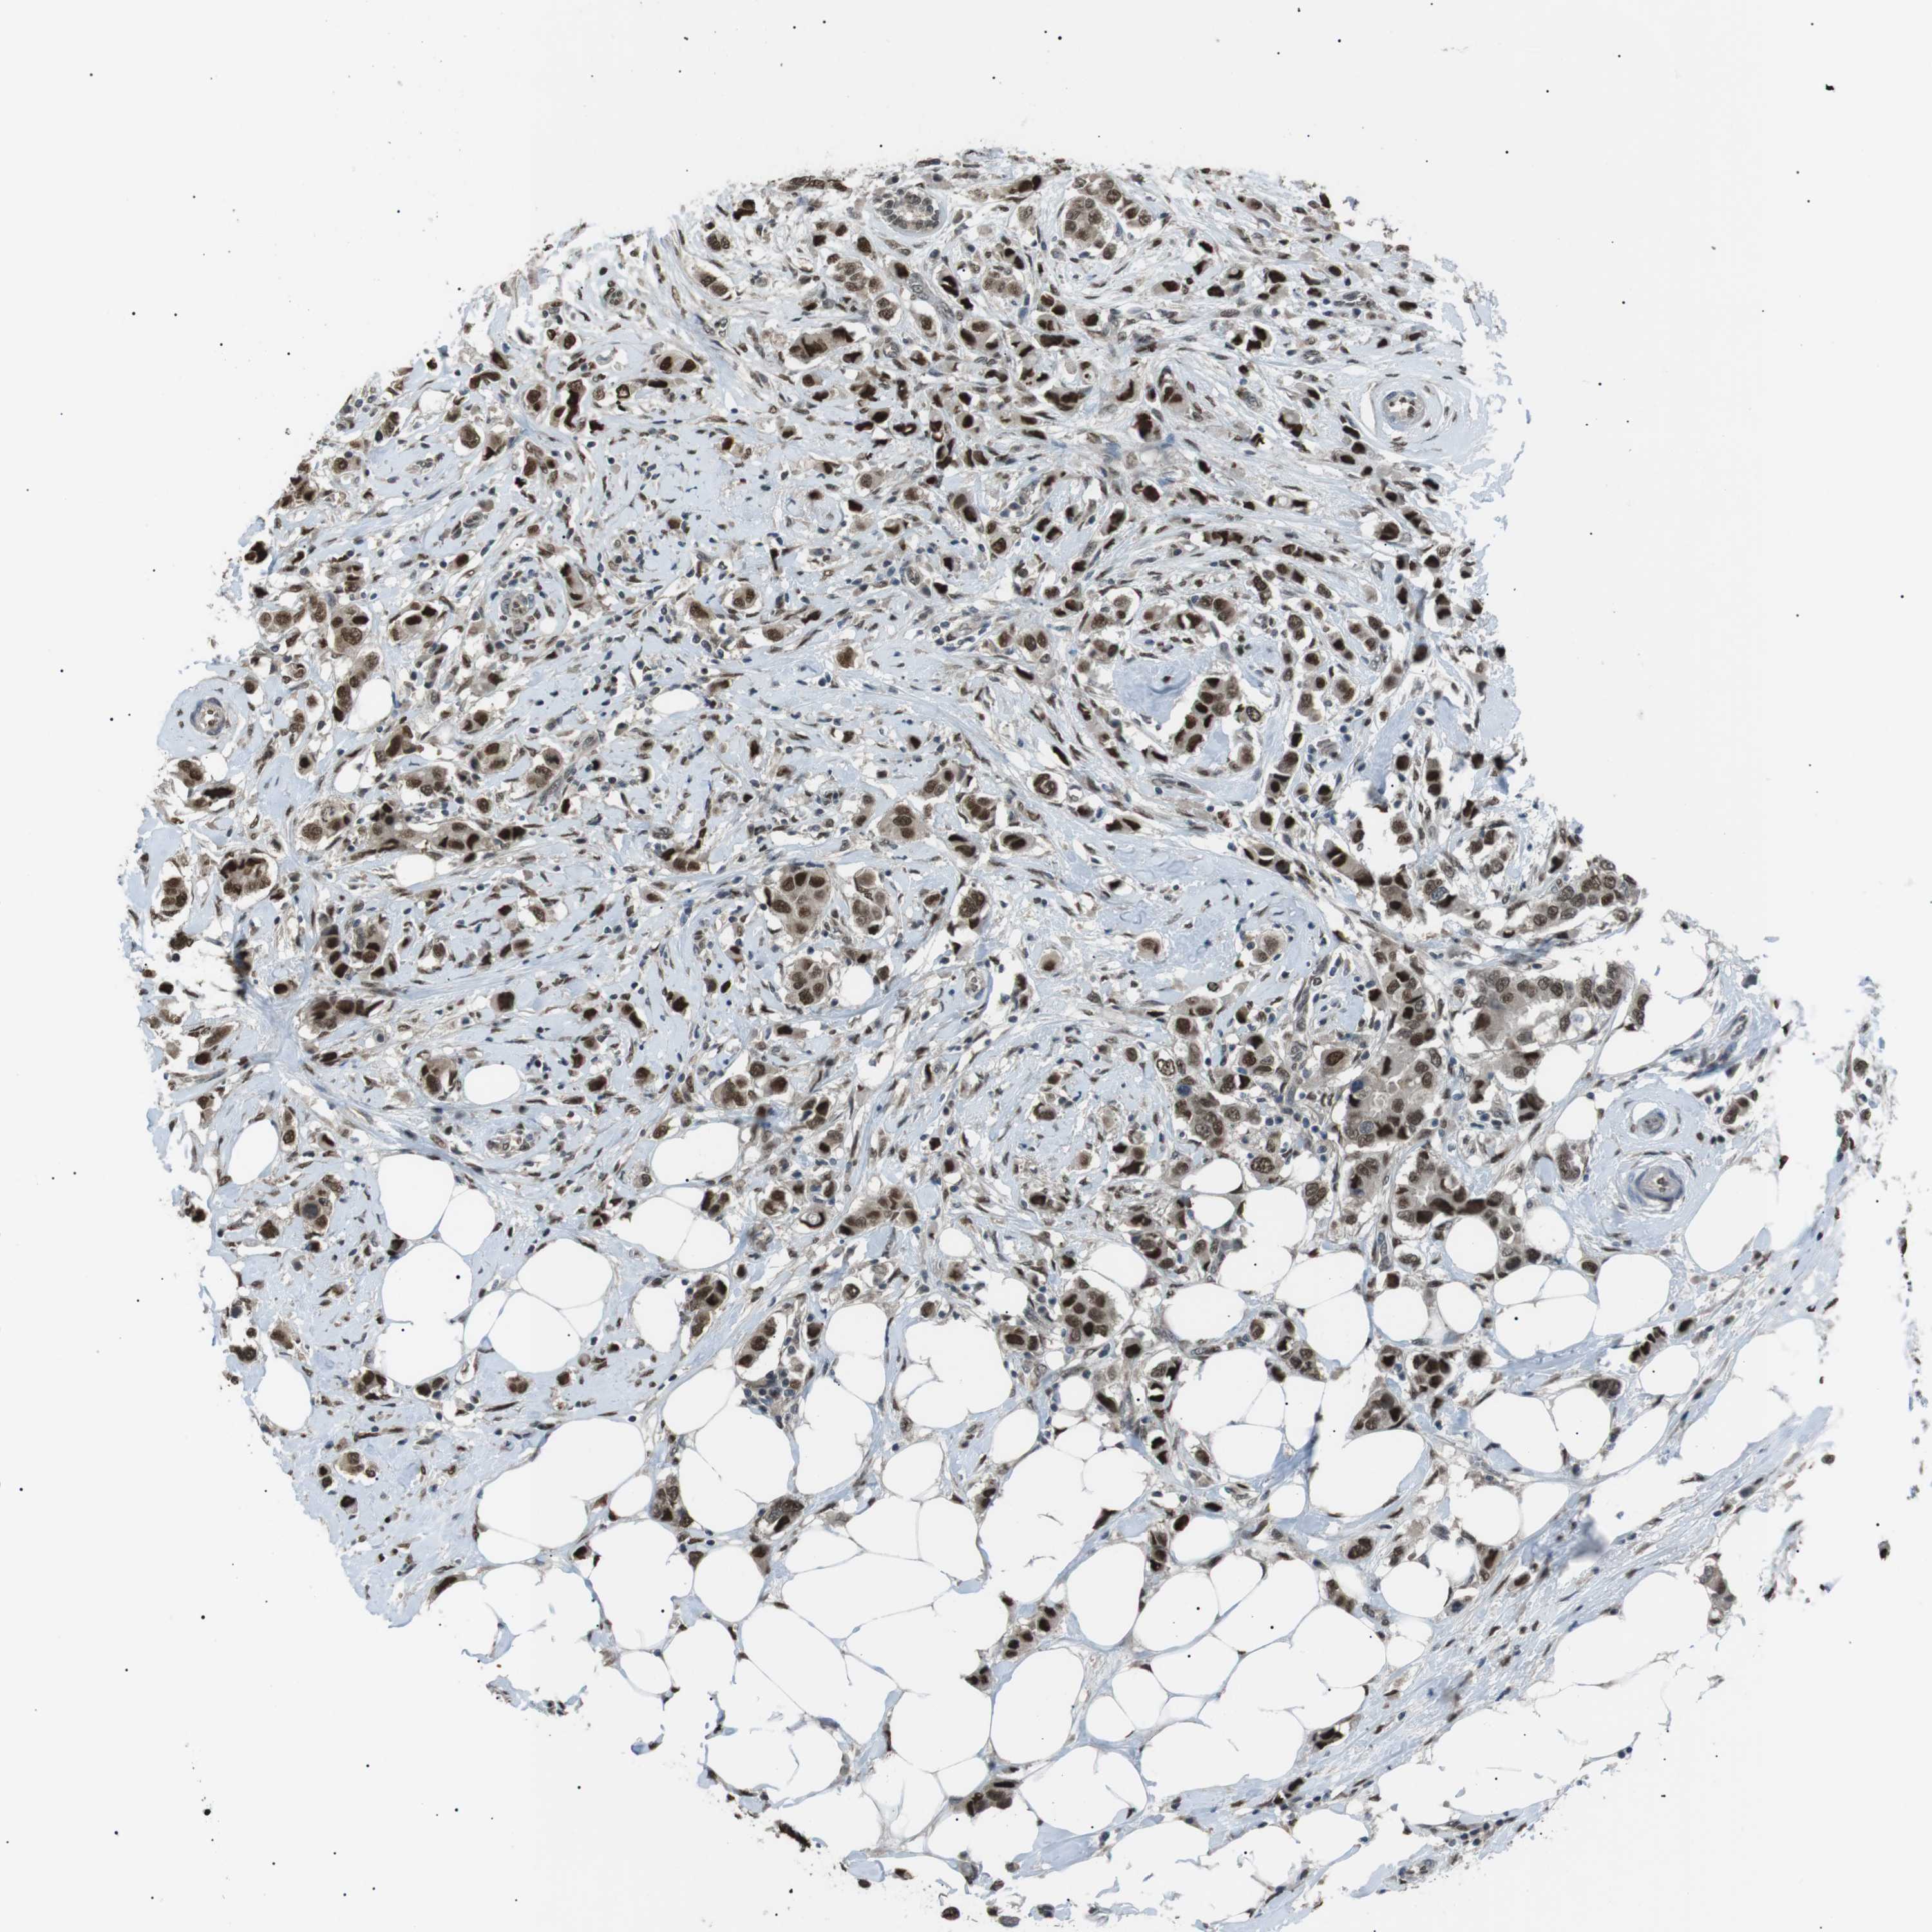

BRCA TCGA BRCA VALIDATION PROTEIN EXPRESSION